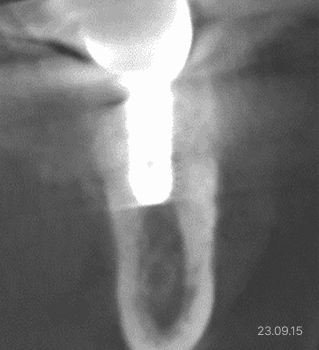

상악동 거상술 · 무절개 임플란트

상악동 거상술 ·

무절개 임플란트

상악동 격벽 · 매우 얇은 잔존뼈